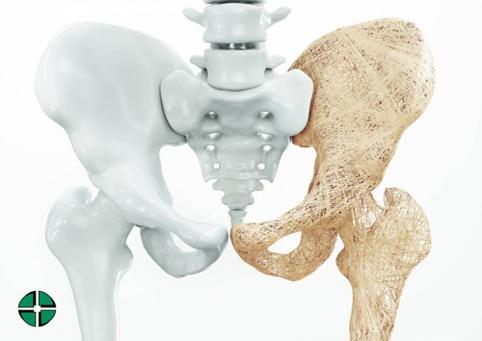

L’osteoporosi è una patologia sistemica, una malattia metabolica del tessuto scheletrico, caratterizzata dalla progressiva e graduale riduzione della massa ossea. Le ossa cominciano a perdere volume perché minerali come sali di calcio, magnesio, fosfati, cominciano a distaccarsi.

Le ossa hanno una densità inferiore e la loro microarchittetura si deteriora. Un osso con meno minerali quindi, si presenta più poroso, e un osso più poroso diventa più fragile, più debole e a risentirne sarà l’intero apparato scheletrico che vedrà diminuita la sua resistenza meccanica e risulterà essere maggiormente predisposto a subire fratture.

La frattura al femore è il caso più drammatico di osteoporosi severa. Essa è indice del fatto che l’osteoporosi ha alterato in maniera significativa la resistenza del nostro tessuto scheletrico aumentando la fragilità ossea portando a questo evento traumatico.